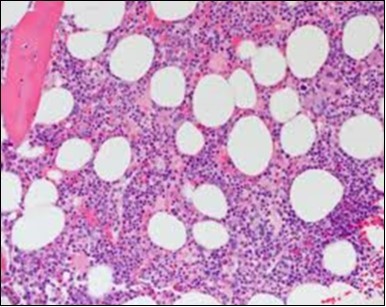

Figure 9.HCL: hairy cells within a bone marrow trephine biopsy(25).

HCL: hairy cells within  a bone marrow trephine biopsy(25).